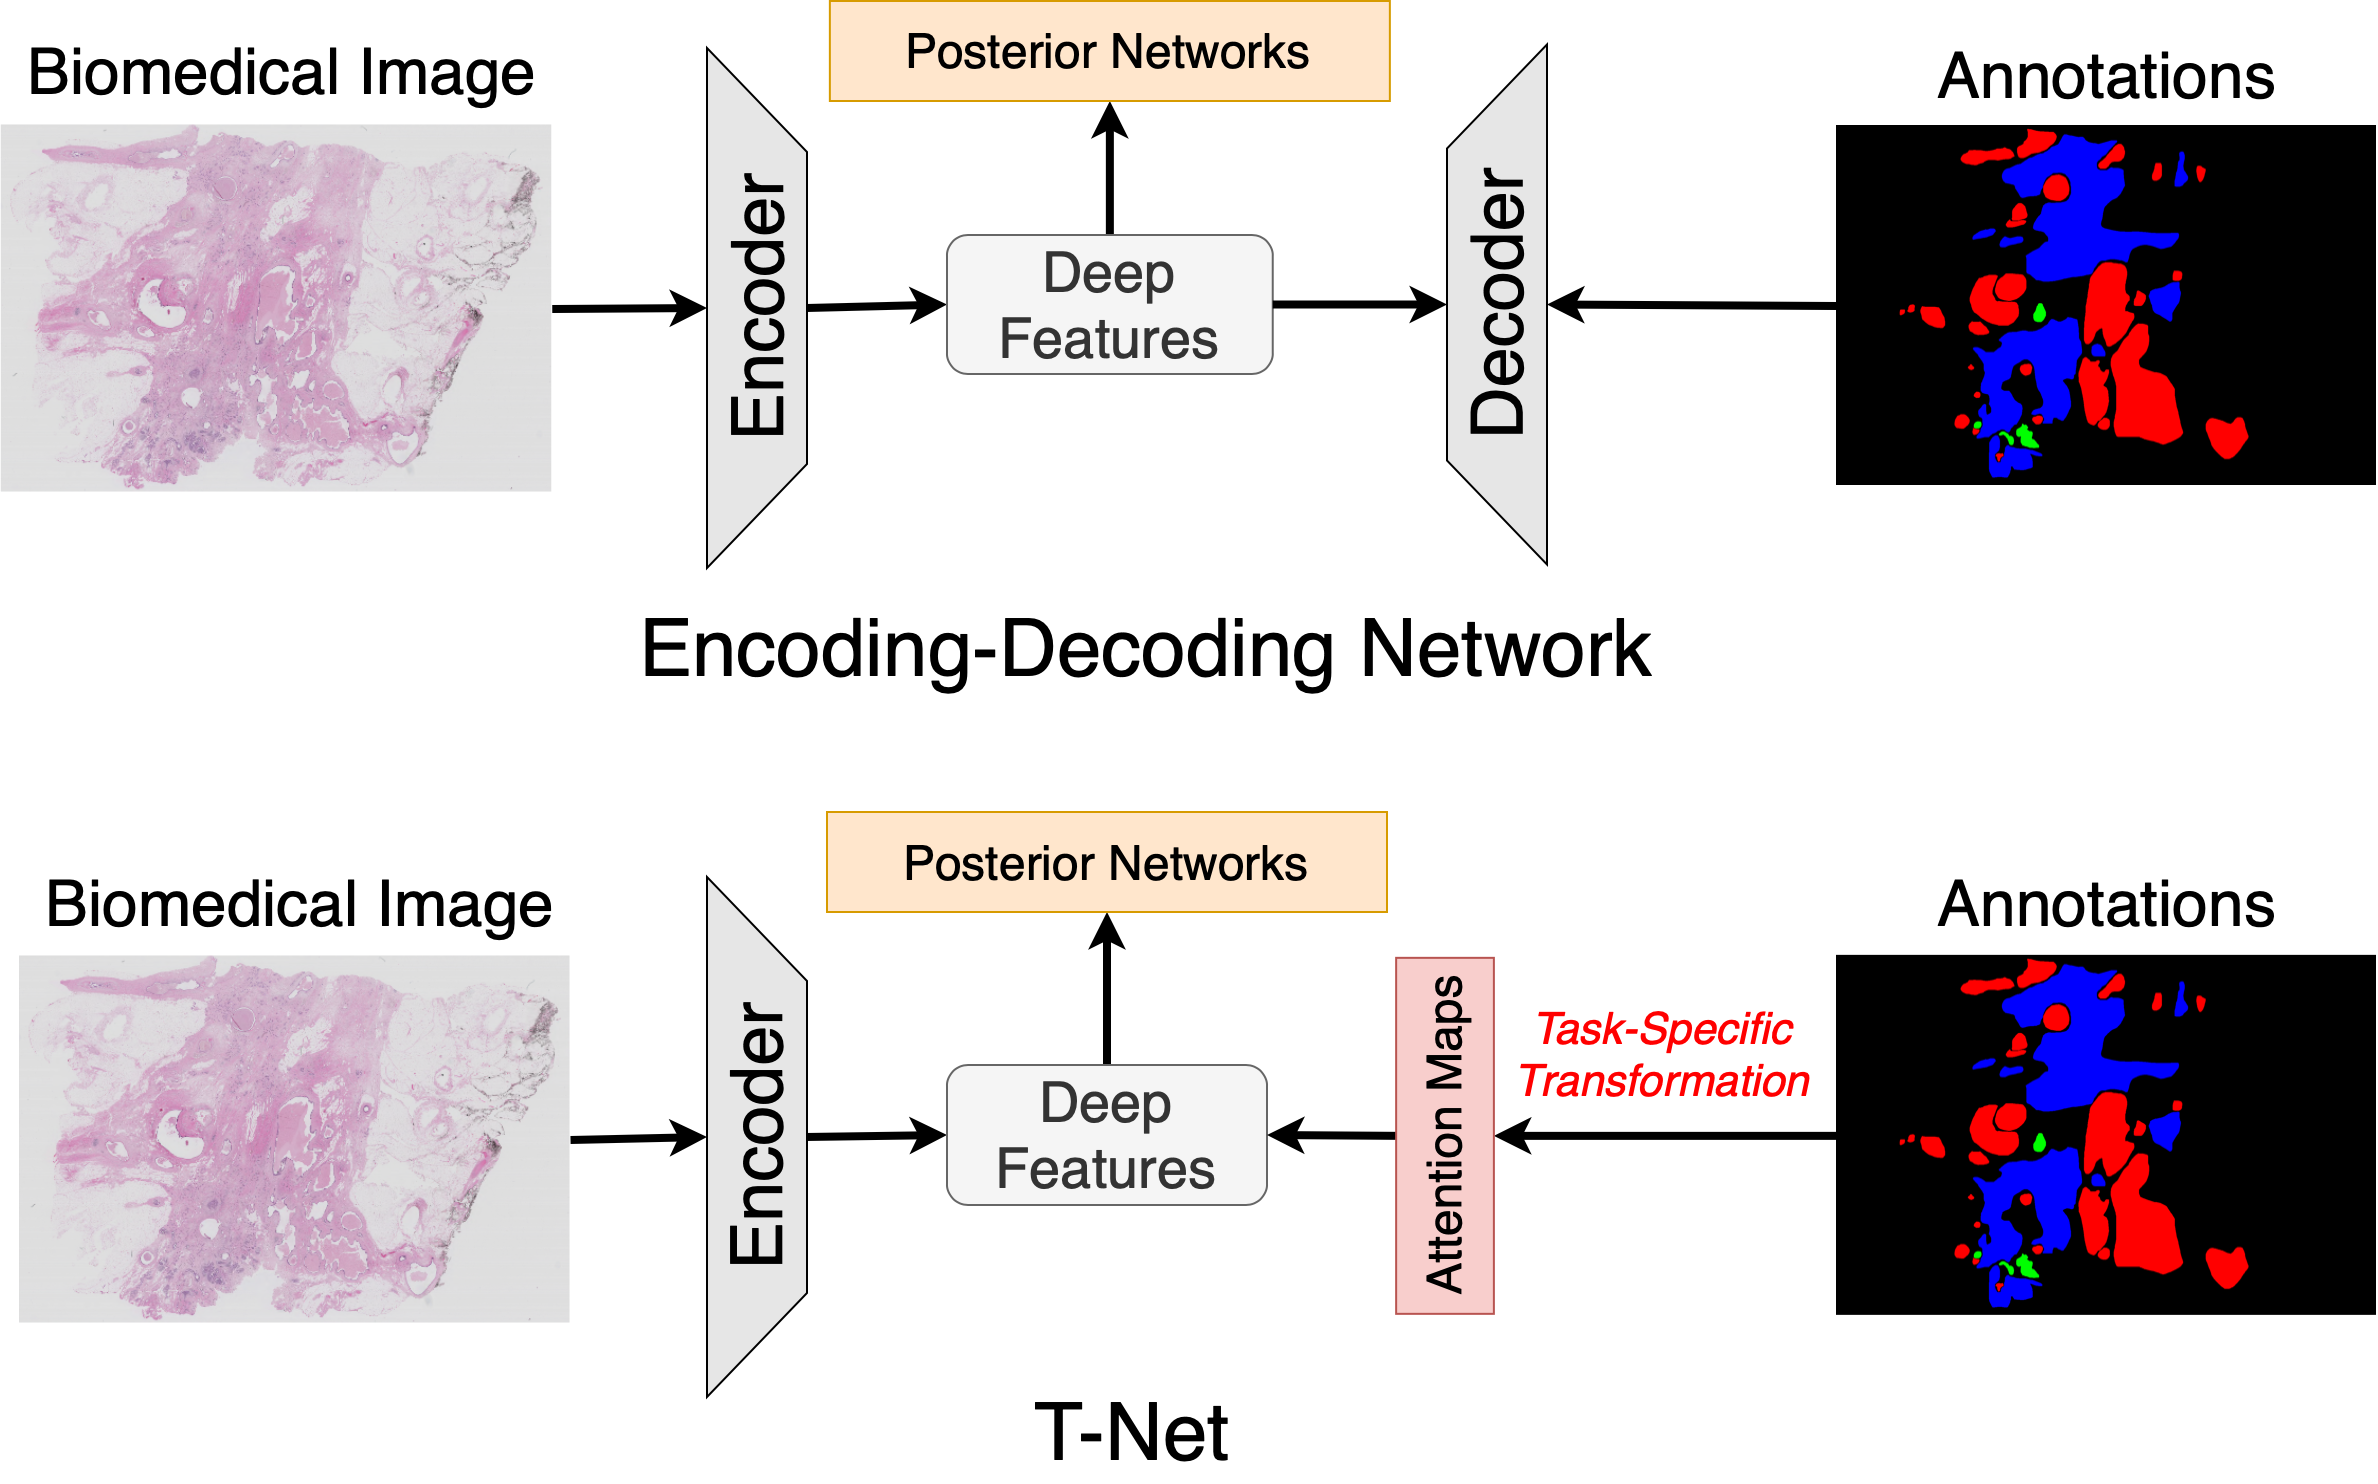

The encoder-decoder network is widely used to learn deep feature representations from pixel-wise annotations in biomedical image analysis. Under this structure, the performance profoundly relies on the effectiveness of feature extraction achieved by the encoding network. However, few models have considered adapting the attention of the feature extractor even in different kinds of tasks. In this paper, we propose a novel training strategy by adapting the attention of the feature extractor according to different tasks for effective representation learning. Specifically, the framework, named T-Net, consists of an encoding network supervised by task-specific attention maps and a posterior network that takes in the learned features to predict the corresponding results. The attention map is obtained by the transformation from pixel-wise annotations according to the specific task, which is used as the supervision to regularize the feature extractor to focus on different locations of the recognition object. To show the effectiveness of our method, we evaluate T-Net on two different tasks, i.e., segmentation and localization. Extensive results on three public datasets (BraTS-17, MoNuSeg and IDRiD) have indicated the effectiveness and efficiency of our proposed supervision method, especially over the conventional encoding-decoding network.

As shown in Fig. 1, our proposed framework, named T-Net, consists of an encoding network to directly learn feature representations from task-specific attention maps and a posterior network to predict the results from the learned features. Specifically, the attention maps are obtained by various transformations from the binary mask of each recognition object according to the task. Furthermore, the posterior network is trained by well-learned features generated by the encoding network to predict the corresponding output, such as binary masks for segmentation or coordinates for object detection. To show the effective feature extraction of our method, we evaluate T-Net on three public datasets for comparison with state-of-the-art methods, where T-Net achieves comparable or superior performance to the leading methods on the open leaderboard. Furthermore, we also set an ablation study to show the impact of different attention maps, which indicates a significant advantage in feature learning over the conventional encoding-decoding network.